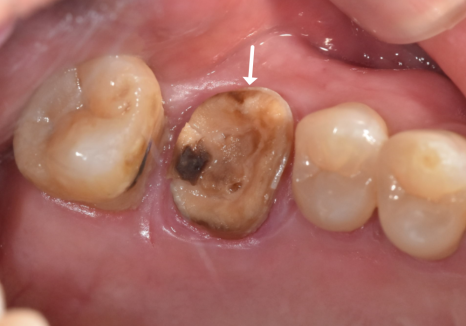

빠진 브릿지를 제거하고 입안을

살펴보니 상황이 생각보다 좋지 않았는데요,

앞니 4개 모두 충치가 깊게 진행되어

검게 삭아버린 상태였고,